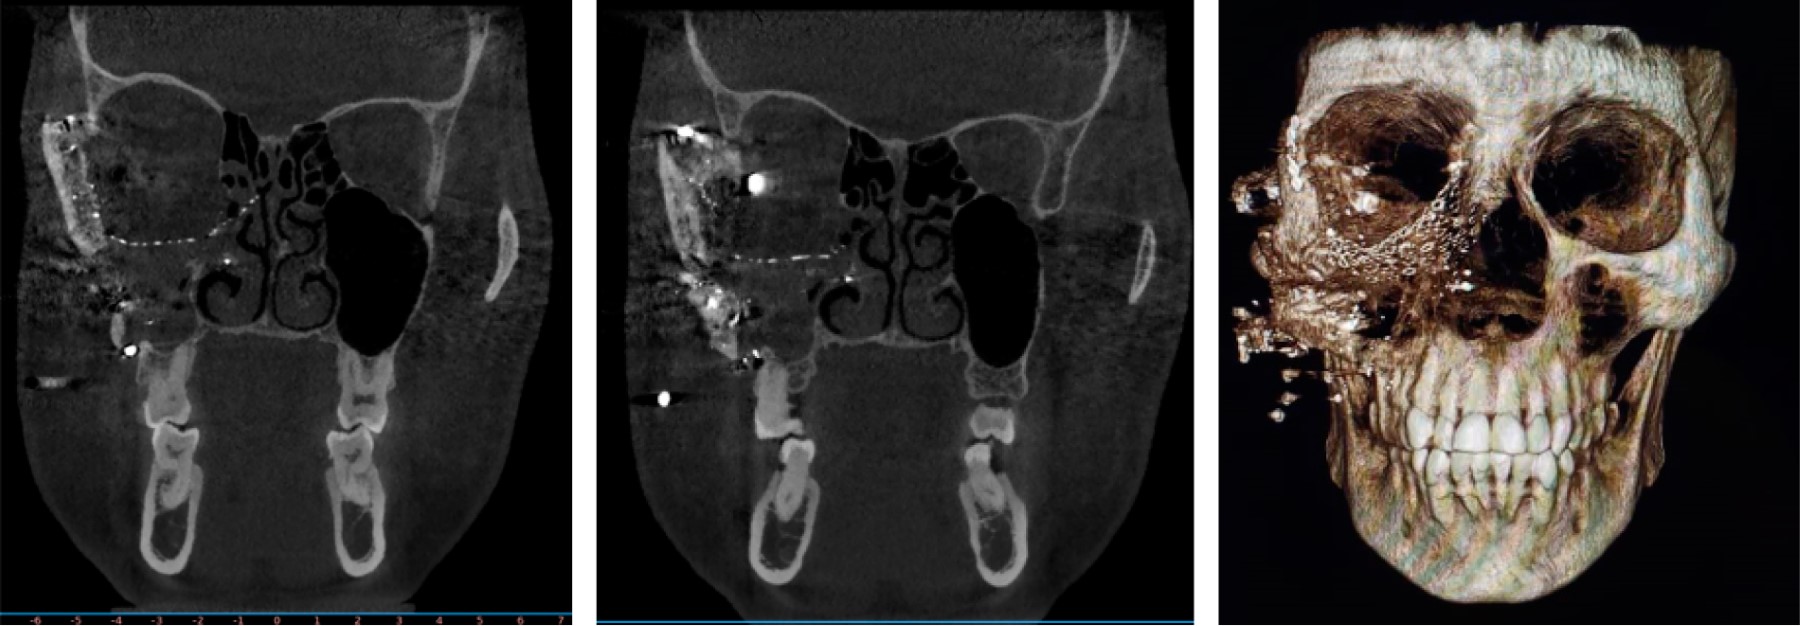

Zygomaticoorbital complex reconstruction with titanium prosthesis: case report

Rodríguez S, Rivas J, Villegas J, García H, Gudiño R, Jaimes J

zygomatic-orbital complex, reconstruction, titanium, temporalis muscle.

Maxillofacial trauma has always been a challenging area for oral and maxillofacial surgeons. Whenever we speak about midface trauma, zygomatic complex is the most common region to treat because of its implications in aesthetic and functional problems that can compromise the nearby eye. In the case of zygomatic complex fractures, most of the time it involves a bone defect in one of its four buttresses, determining the need to reconstruct. Custom made titanium prosthesis offers a lot of advantages in handling and installation, making it easier to adapt in the required region.

Figure 2